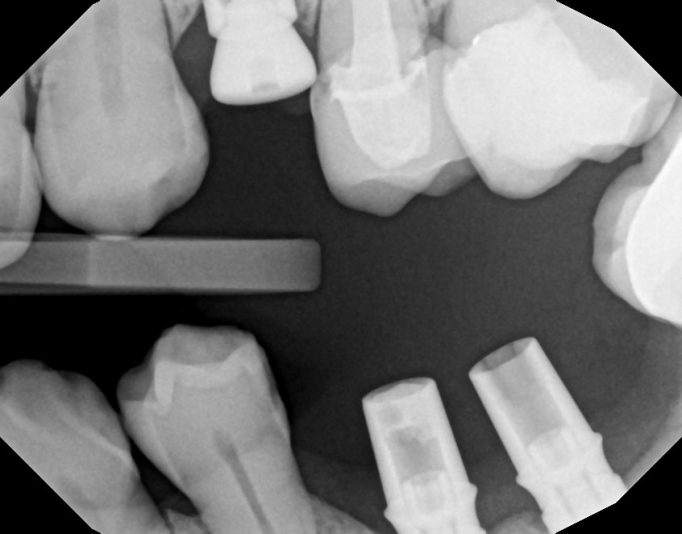

Hey guy, I’m still pretty new to implants. I’ve placed about 30. Looking for suggestions to improve. This is my most recent one. I chose 9 mm implant due to the proximity to the nerve. My main goal was to engage natural bone beyond the apex of the socket without getting too close to the nerve. I used the Densah burs, mostly in OD mode. and…